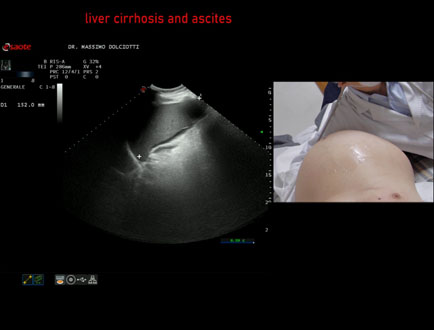

Data inserimento: 24/05/2010

Ecografia del: 04/05/2010

Strumento: Sonosite

Sonda: Convex 3,5 Mhz

Età Paziente:  M 74 anni

Motivazione dell'esame: incremento del volume dell'addome.

Commento all'esame: le immagini documentano l'abbondante ascite, il fegato ad ecostruttura disomogenea, nodulare, con profili marcatamente irregolari. Splenomegalia.